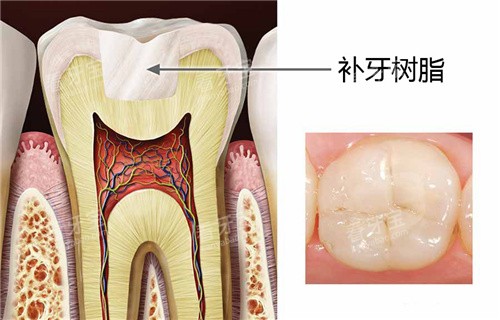

但2026年的南通口腔市场已大不同:从168元的树脂补牙到1080元的全瓷修复,价格透明得像超市价签,连材料优缺点都写得明明白白。本文结合南通较新口腔价目表和真实实例,带你拆解补牙价格的“底牌”,手把手教你避开“低价陷阱”。

南通补牙价格已形成“金字塔”结构:基础款树脂补牙168元起,中端纳米树脂300-600元,高端全瓷修复1080元起。这价格看似亲民,但“起”字背后藏着门道——比如某诊所168元的补牙可能用较普通的树脂,若想选耐磨性更好的材料,价格直接跳到368元。

真实实例:市民王女士在某连锁口腔补后牙,医生推荐“美国Z350纳米树脂”,报价562元。她对比后发现,普通树脂补牙虽便宜,但3个月后边缘发黄,而纳米树脂用了2年仍洁白如新。“贵有贵的道理,省下的钱不够以后重补的。”王女士说。

问清材料品牌:进口树脂(如3M Z250/Z350)比国产更耐磨,但价格高20%-50%;